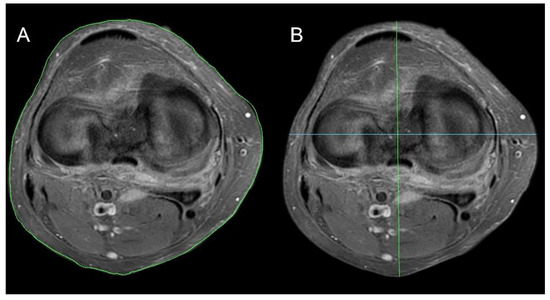

2.5. Knee Parameter Measurements